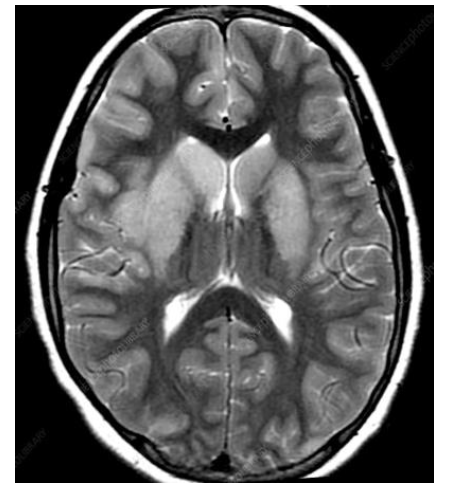

Case Presentation: A female patient in her 70s, with a history notable for hypothyroidism who initially presented to an outside hospital with complaints of left-hand paresthesia, numbness, and dizziness. She underwent an extensive work up for CVA with no acute findings on non-contrast MRI brain or cervical spine. During her hospital course she developed worsening encephalopathy, and rapidly progressing quadriparesis, the patient was treated with a 5-day course of IVIG, for a concern of Guillain-Bare syndrome (GBS). However, CSF findings were notably inconsistent with GBS. Her symptoms were presumed to be due to a viral etiology in the setting of pleocytosis seen on CSF. Due to a high risk of decompensation, the patient was transferred to a higher level of care, where she underwent repeat MRI imaging with and without contrast of the brain and spine, as well as a repeat lumbar puncture for additional CSF studies. She was started on empiric Acyclovir, Ceftriaxone and Doxycycline for possible HSV and tick- borne infection, respectively. She also received a trial of pulse dose steroids with significant clinical improvement. Although, most of her workup returned negative, her EBV PCR was positive, confirming EBV encephalitis. Given the patients’ significant clinical improvement of encephalopathy and paresis on steroids, she was transitioned to a prednisone taper and discharged to rehab with a follow up with neurology and infectious disease.